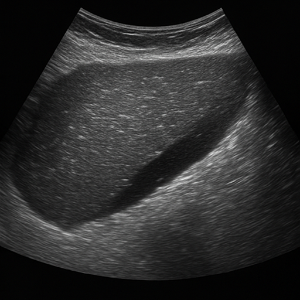

복부 종양과 복수

간, 신장, 또는 다른 복부 장기에 생긴 혹들은 초음파에서 덩어리로 보여요. 가끔은 원래 장기가 아닌 곳에 생긴 종양도 보여요. - 복수 (복강 내 물)

배에 물이 고이는 현상이에요. 초음파로 액체가 있는 곳을 쉽게 볼 수 있어서, 복수가 있는지 확인할 때 매우 유용해요.